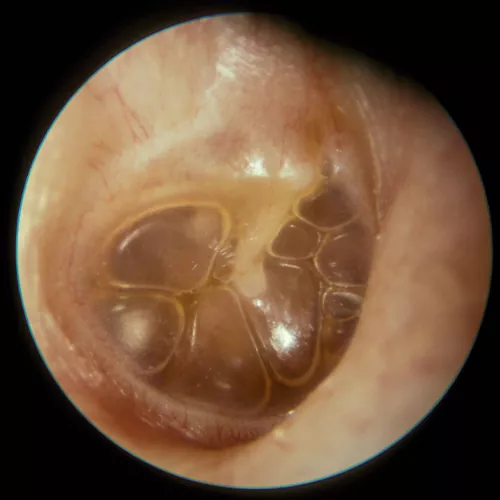

La otoscopia es la prueba fundamental para el diagnóstico, siendo definitiva en una parte importante de los casos. Existen muchas anomalías en la membrana timpánica asociadas a la otitis serosa. Por lo general, muestra un tímpano íntegro, edematizado y opaco con un aumento de la vascularización radial, y puede estar en posición normal, abombado o retraído. En los procesos de corta evolución la coloración suele ser rojiza, generalmente con una membrana engrosada. Sin embargo en los casos crónicos el aspecto suele ser azulado, resultado del depósito de hemosiderina en el exudado, y la membrana suele estar adelgazada y atrófica, con tendencia a la retracción, pudiendo desencadenar en una otitis adhesiva. En los casos en que el tímpano conserva su transparencia, es posible observar en ocasiones niveles o burbujas (indicativo de que la trompa funciona parcialmente).